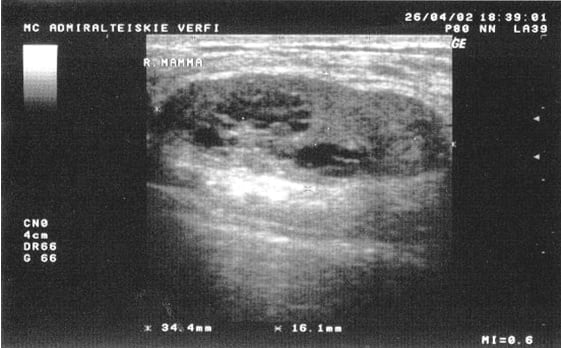

УЗИ грудных желёз у пациентов мужчин назначается в случае разрастания жировой ткани или определения при пальпации новообразования в области груди. Эти признаки могут указывать на раковые опухоли или гинекомастию, которая чревата серьёзными психологическими проблемами у пациента. Для определения используют процедуру ультразвукового исследования. На сегодняшний день это самый безопасный и абсолютно безболезненный метод исследования, который эффективно показывает состояние внутренних органов и тканей наглядно, позволяя сделать выводы о здоровье мужчины.

Здоровая железа груди у мужчин представляет собой жировую ткань с мало развитыми млечными протоками и маленькими лимфоузлами. Нередко грудь мужчины изменяет свой размер и форму при похудении или, наоборот, наборе веса. Однако патологией считается, если произошло разрастание железистой ткани, фиброзе или образовании крупных узлов. Ультразвуковая диагностика считается одним из самых простых и результативных способов исследование.

Главным образом сделать УЗИ грудных желёз рекомендуется пациентам, которые заметили у себя изменение формы или размера груди. Чаще всего причиной называют гинекомастию, ложную или истинную.

УЗИ-диагностика позволяет определить причину развития патологии. Это происходит либо из-за разрастания железистой ткани вследствие нарушения гормонального обмена, либо из-за повышения количества жировой ткани.

У мужчин редко, но отмечают случаи развития злокачественных опухолей.

Ультразвук помогает определить состояние грудных желёз и выявить причины разрастания. Его проводят вместе с основными анализами на различные патологии.